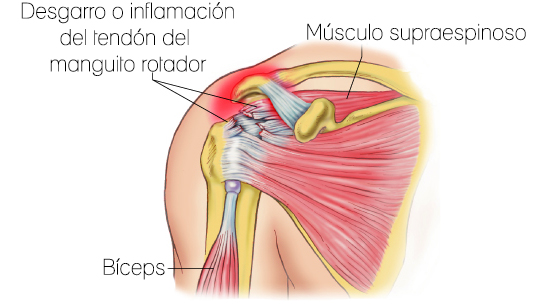

Desgarro del manguito rotador

El manguito de los rotadores (RC) es un grupo de 4 músculos: supraespinoso, infraespinoso, redondo menor y subescapular. El RC asiste tanto el control del motor grueso y fino del brazo.

La tendinitis del manguito rotador

Este trastorno se caracteriza por el dolor y la rigidez en el hombro asociado con los movimientos del brazo hacia atrás y hacia arriba, y la debilidad del manguito de los rotadores músculos. Las posibles causas incluyen la hinchazón o el desgarro de los tejidos blandos del manguito rotador, hombro hueso conjunta espuelas / anormalidades, y la mala postura hombro.